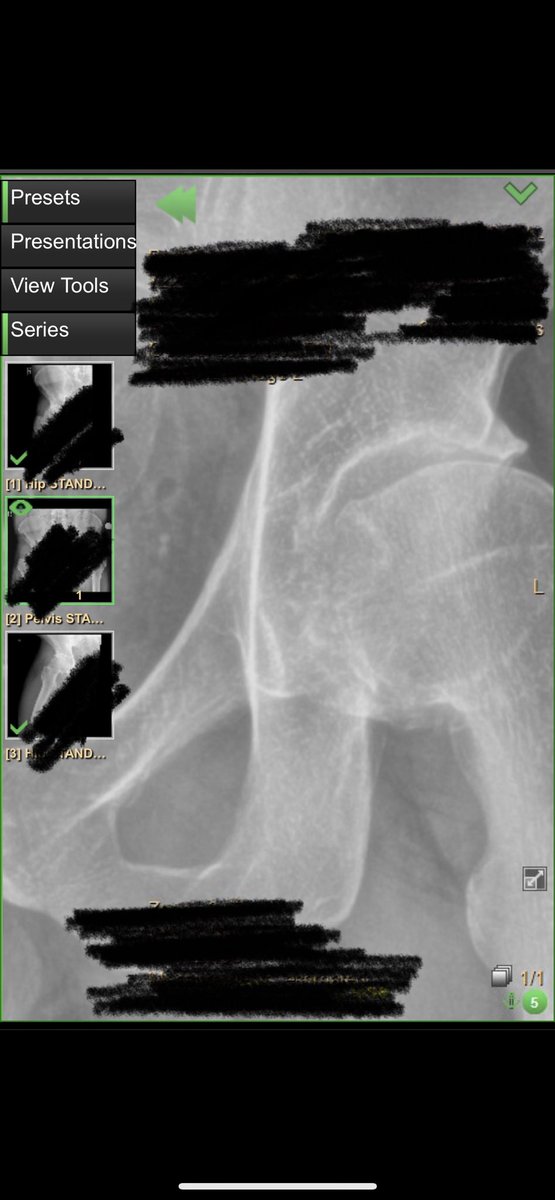

Over the past few years I’ve been having consistent pain in my hips. Extremely limited range of motion, and arthritic flare ups that left me feeling useless from a physical point of view. Literally felt like I was 90. It started affecting my mood, my body, my wellbeing. I had trouble running around with my young boys, picking things up off the ground, sitting and working, exercising , etc. I tried physio, yoga, you name it. I’m 38 years old. Today I had BOTH my hips replaced. And it went great. I’m so excited to have a new lease on movement, pain free. The boring marketer is a bionic man! While I’m OOO this week, I’ve never felt more confident in our amazing team to keep delivering results to clients and operating without me. A few years ago, stepping “out of the business” would have been a non starter. Check out the before and after pics: I’m amazed at what they can do these days. Grateful for my doc and all the great care and especially my wife who hasn’t left my side!

The Boring Marketer tweet mediaThe Boring Marketer tweet media